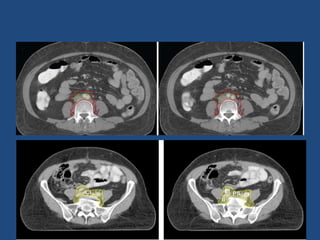

• Start contouring iliac vessels from aortic bifurcation down till

the appearance of femoral head.

• Uniformly, pelvic blood vessels are given a margin of 7mm.

The upper border is maintained at aortic bifurcation.

• The contour is extended around common iliac vessels

posteriorly and laterally so as to include connective tissue

between iliopsoas muscles and lateral surface of vertebral

body.

• All visible nodes (contoured as GTV node) are given a margin

of 10mm to create CTV node.

• Muscle and bone are excluded from CTV N.